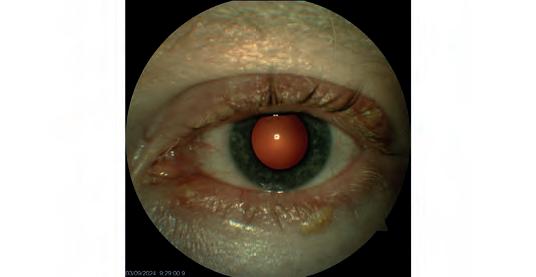

A retinal detachment diagnosed by Queensland optometrist Peter Choc on his Optos Daytona.

A secondary retinal detachment.

Images: Gladstone Vision.